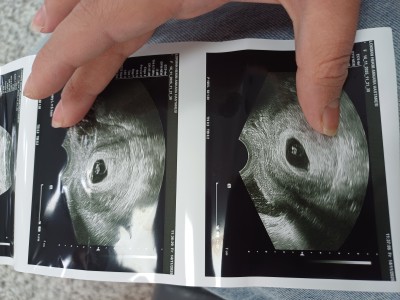

Canim benimki de bir benzerini yaşıyorum suan son adet günüm 21 Eylül kese ekranda zor gözüküyor resmen o kadar küçük ve belli belirsizki anlatamam en son 6+4 de gittim bebek yeni oluşmuş dedi ekrandan kalp atışını görüyorum ama makineye vurdu hiçbir şey duyulmadı bana da 1 2 hafta sonra gel dedi bir sorun var mi dedim bir sorun bence yok dedi kanama filan olursa gel dedi ama şükür bir şeyim yok bende suan 7+6 m 9+1 e denk geliyo gideceğim zaman inşallah o zaman duyarım bende senin gibi merak ve beklenti içindeyim inşallah hayırlı haberler alırız oglumda igne ile olmuştu gunu gününe uyumluydu bu doğal kendiliğinden oldu saglik ocağı hemsiresine sordum ovulasyonun gec olmuştur takılma boyle şeylere dedi benim bebeğim de 3 mm çıkmıştı bak kese ve bebeğin görüntüsünü koydum profilimde en altlara inersen oğlumun kesesi de gözüküyor ama o cok belli ve ikisi de aynı doktor